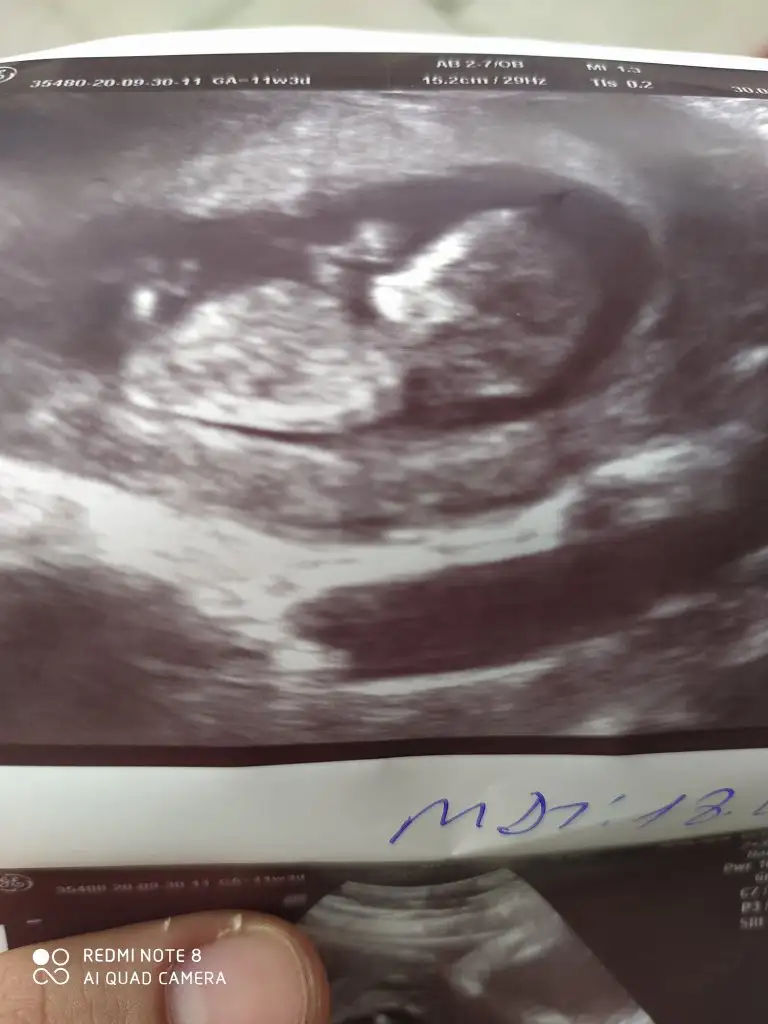

Ne zaman ogrenceksiniz cinsiyeti. Bazı arkadaşlarım 12 haftada öğrendi

Ya 12.haftada kız gibi dedi ama bacağıyla kapattı. Yani kesin bir şey söylemedi ve bence de o haftalarda çok erken. Yanılmalar çok oluyo. Bir ay sonraya randevu verdi cinsiyeti için. Suan yani hala net değil 😶

Öyle canim tabi banada 16 haftada gel dedi. Oğlumdada ozaman net öğrenmiştik. Hayırlısı bakalım☺️